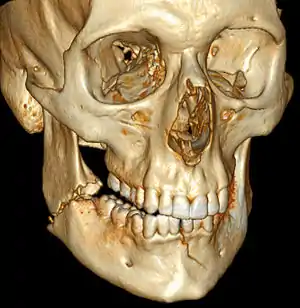

| 3D computed tomographic image of a mandible fracture in two places. One is a displaced right angle fracture and the other is a left parasymphyseal fracture. | |

Computed tomography is the most sensitive and specific of the imaging techniques. The facial bones can be visualized as slices through the skeletal in either the axial, coronal or sagittal planes. Images can be reconstructed into a 3-dimensional view, to give a better sense of the displacement of various fragments. 3D reconstruction, however, can mask smaller fractures owing to volume averaging, scatter artifact and surrounding structures simply blocking the view of underlying areas.

3D CT reconstruction of mandible fracture, white arrow marks fracture, red arrow marks moderate displacement and open bite